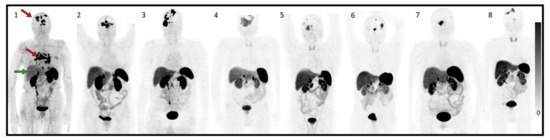

| 1 | 74 | F | 3 years | Multiple meningioma, metastasis | II | Surgery, EBRT, SRS, Sandostatine-Everolimus | 15–20% | N/A | motor deficit, confusion | 2 |

| 2 | 85 | F | 17 years | multiple meningioma; subcutaneous frontal lesion | II | Surgeryx3, SRSx2, EBRT | 15% | N/A | visual disturbance | 2 |

| 3 | 67 | M | 9 years | multiple meningioma | II | Surgeryx2, EBRT, SRS, Sandostatine-Everolimus | N/A | 2% | left hemiparesis | 2 |

| 4 | 72 | M | 19 years | multiple meningioma | II | Surgeryx2, EBRT, SRS, Sandostatine-Everolimus | N/A | 25% | visual disturbance; frontal syndrome | 1 |

| 5 | 60 | M | 9 years | multiple meningioma, metastasis | III; II | Surgeryx2, parotidectomy, EBRT | 30–40% | 10% | asthenia, attention deficit disorder | 1 |

| 6 | 76 | M | 15 years | multiple meningioma | II | Surgeryx5, EBRT, SRSx3 | 10–15% | 25; 20% | none | 0 |

| 7 | 73 | F | 15 years | multiple meningioma | II | Surgeryx2, EBRT, SRS | 10% | N/A | visual disturbance, ptosis, trigeminal neuralgia | 1 |

| 8 | 67 | M | 11 years | multiple meningioma | II | Surgery, EBRT | N/A | N/A | left upper limb deficiency, | 1 |

| Krenning Score | WHO Grade | SUVmax Pretreatment | Cumulative Dose (GBq) | Best Radiologic Response | PFS 2D RANO Criteria | |

| 1 | 3 | II | 7.4 | 10.6 | PD | 2 months |

| 2 | 3 | II | 26.3 | 29.6 | SD | 10 months |

| 3 | 3 | II | 45 | 29.6 | SD | 17 months |

| 4 | 2 | II | 14.5 | 29.6 | SD | 16 months |

| 5 | 2 | III; II | 12.3 | 29.6 | SD | not reached at 12 months |

| 6 | 3 | II | 16 | 29.6 | SD | not reached at 9 months |

| 7 | 3 | II | 16.8 | 29.6 | SD | N/A * |

| 8 | 3 | II | 15.4 | 29.6 | SD | not reached at 16 months |